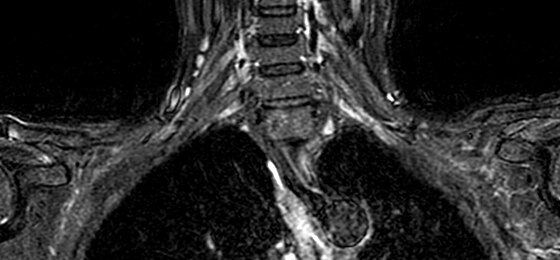

Make no substitutes for image quality

Clearly consistent images

Simply better compared to conventional coil technology.